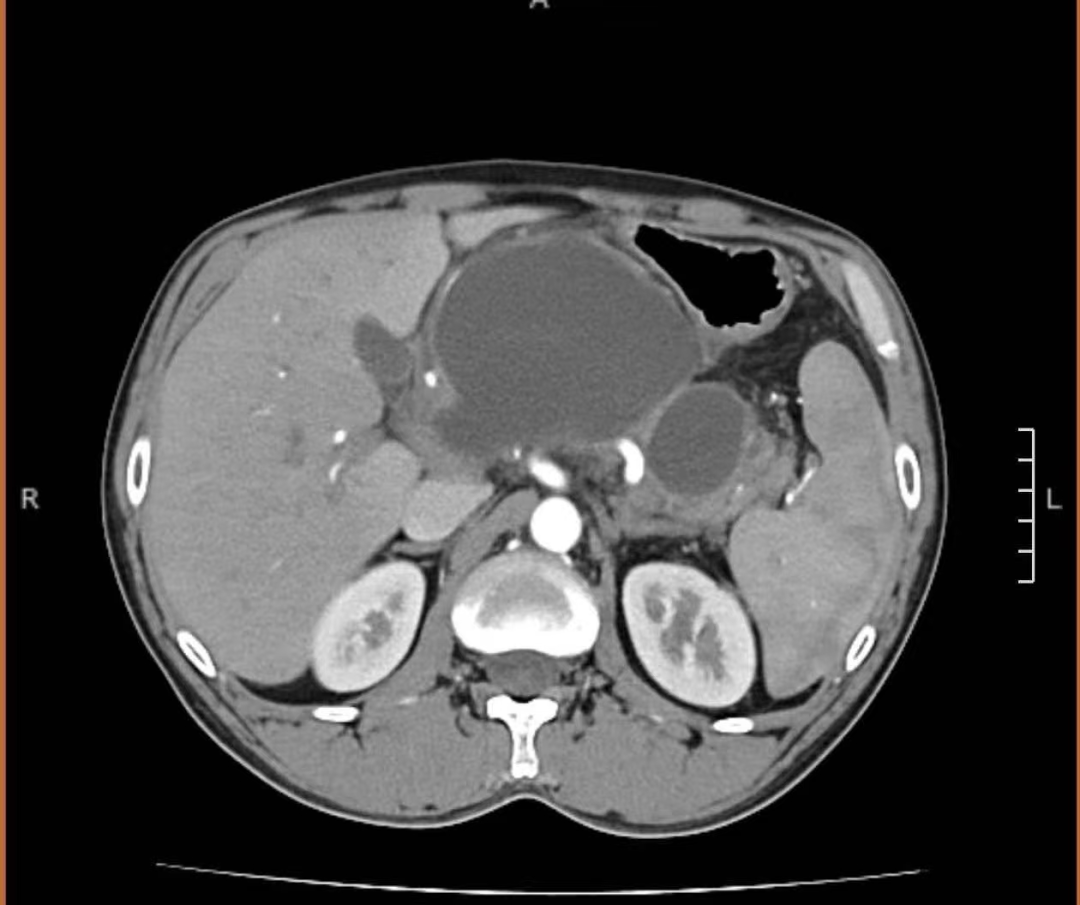

患者为青年男性,因“上腹部持续性胀痛2天”入住我院普外一病区,腹部增强CT检查提示:考虑急性胰腺炎并假性囊肿形成,胰胃间隙存在一直径约10厘米的假性囊肿,已对周围脏器形成明显压迫,引发腹胀不适。如不及时干预,囊肿可能继续增大、引发感染甚至破裂,危及患者健康。

患者术前CT

本次手术在刘哲教授指导下完成,刘哲通过超声内镜扫查胰腺:胰胃间隙可见一巨大囊性病变,较大长径约10.1cm,其内可见点片状高回声信号,彩色多普勒显示内部未见明显血流信号,采用一次性囊肿切开刀于胃体上段大弯侧电切电凝后;进入囊肿腔内,引入导丝,通过一次性囊肿切开刀再次扩大切口,抽出淡褐色液体送常规、生化、淀粉酶、肿瘤标记物及培养,经斑马导丝置入10Fr双猪尾支架1根及鼻胆管一根于囊腔内,随后超声评估支架及鼻胆管位于囊腔内,可见囊腔明显缩小,穿刺道未见活动性出血。实现了超声实时引导,安全穿刺,双路引流设计,提升疗效,该术式尤其适合囊肿较大、感染风险高的病例,体现我院在处理复杂性囊肿中的个体化策略能力。